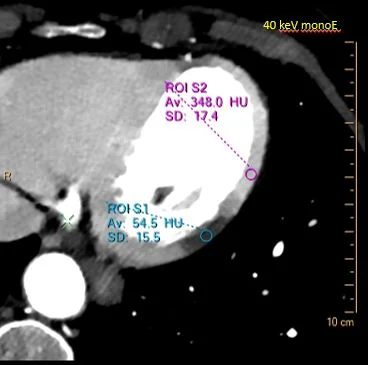

The attenuation of the hypo-enhancing area is about 55 HU on conventional images, and normal myocardium is about 132 HU, giving a difference of about 77 HU (there is a standard deviation). Now look at 40 keV image: the attenuation difference is almost 300 HU, with nearly the same amount of noise. On the iodine map, the area in question has almost no iodine uptake, where normal myocardium has about 3.5 mg/ml of iodine. This is ischemia in the circumflex territory, which I tell the ER.

Now some numbers. Notice the attenuation difference between MI and normal perfused myocardium on conventional scan.

40 keV: Attenuation difference nearly quadrupled!